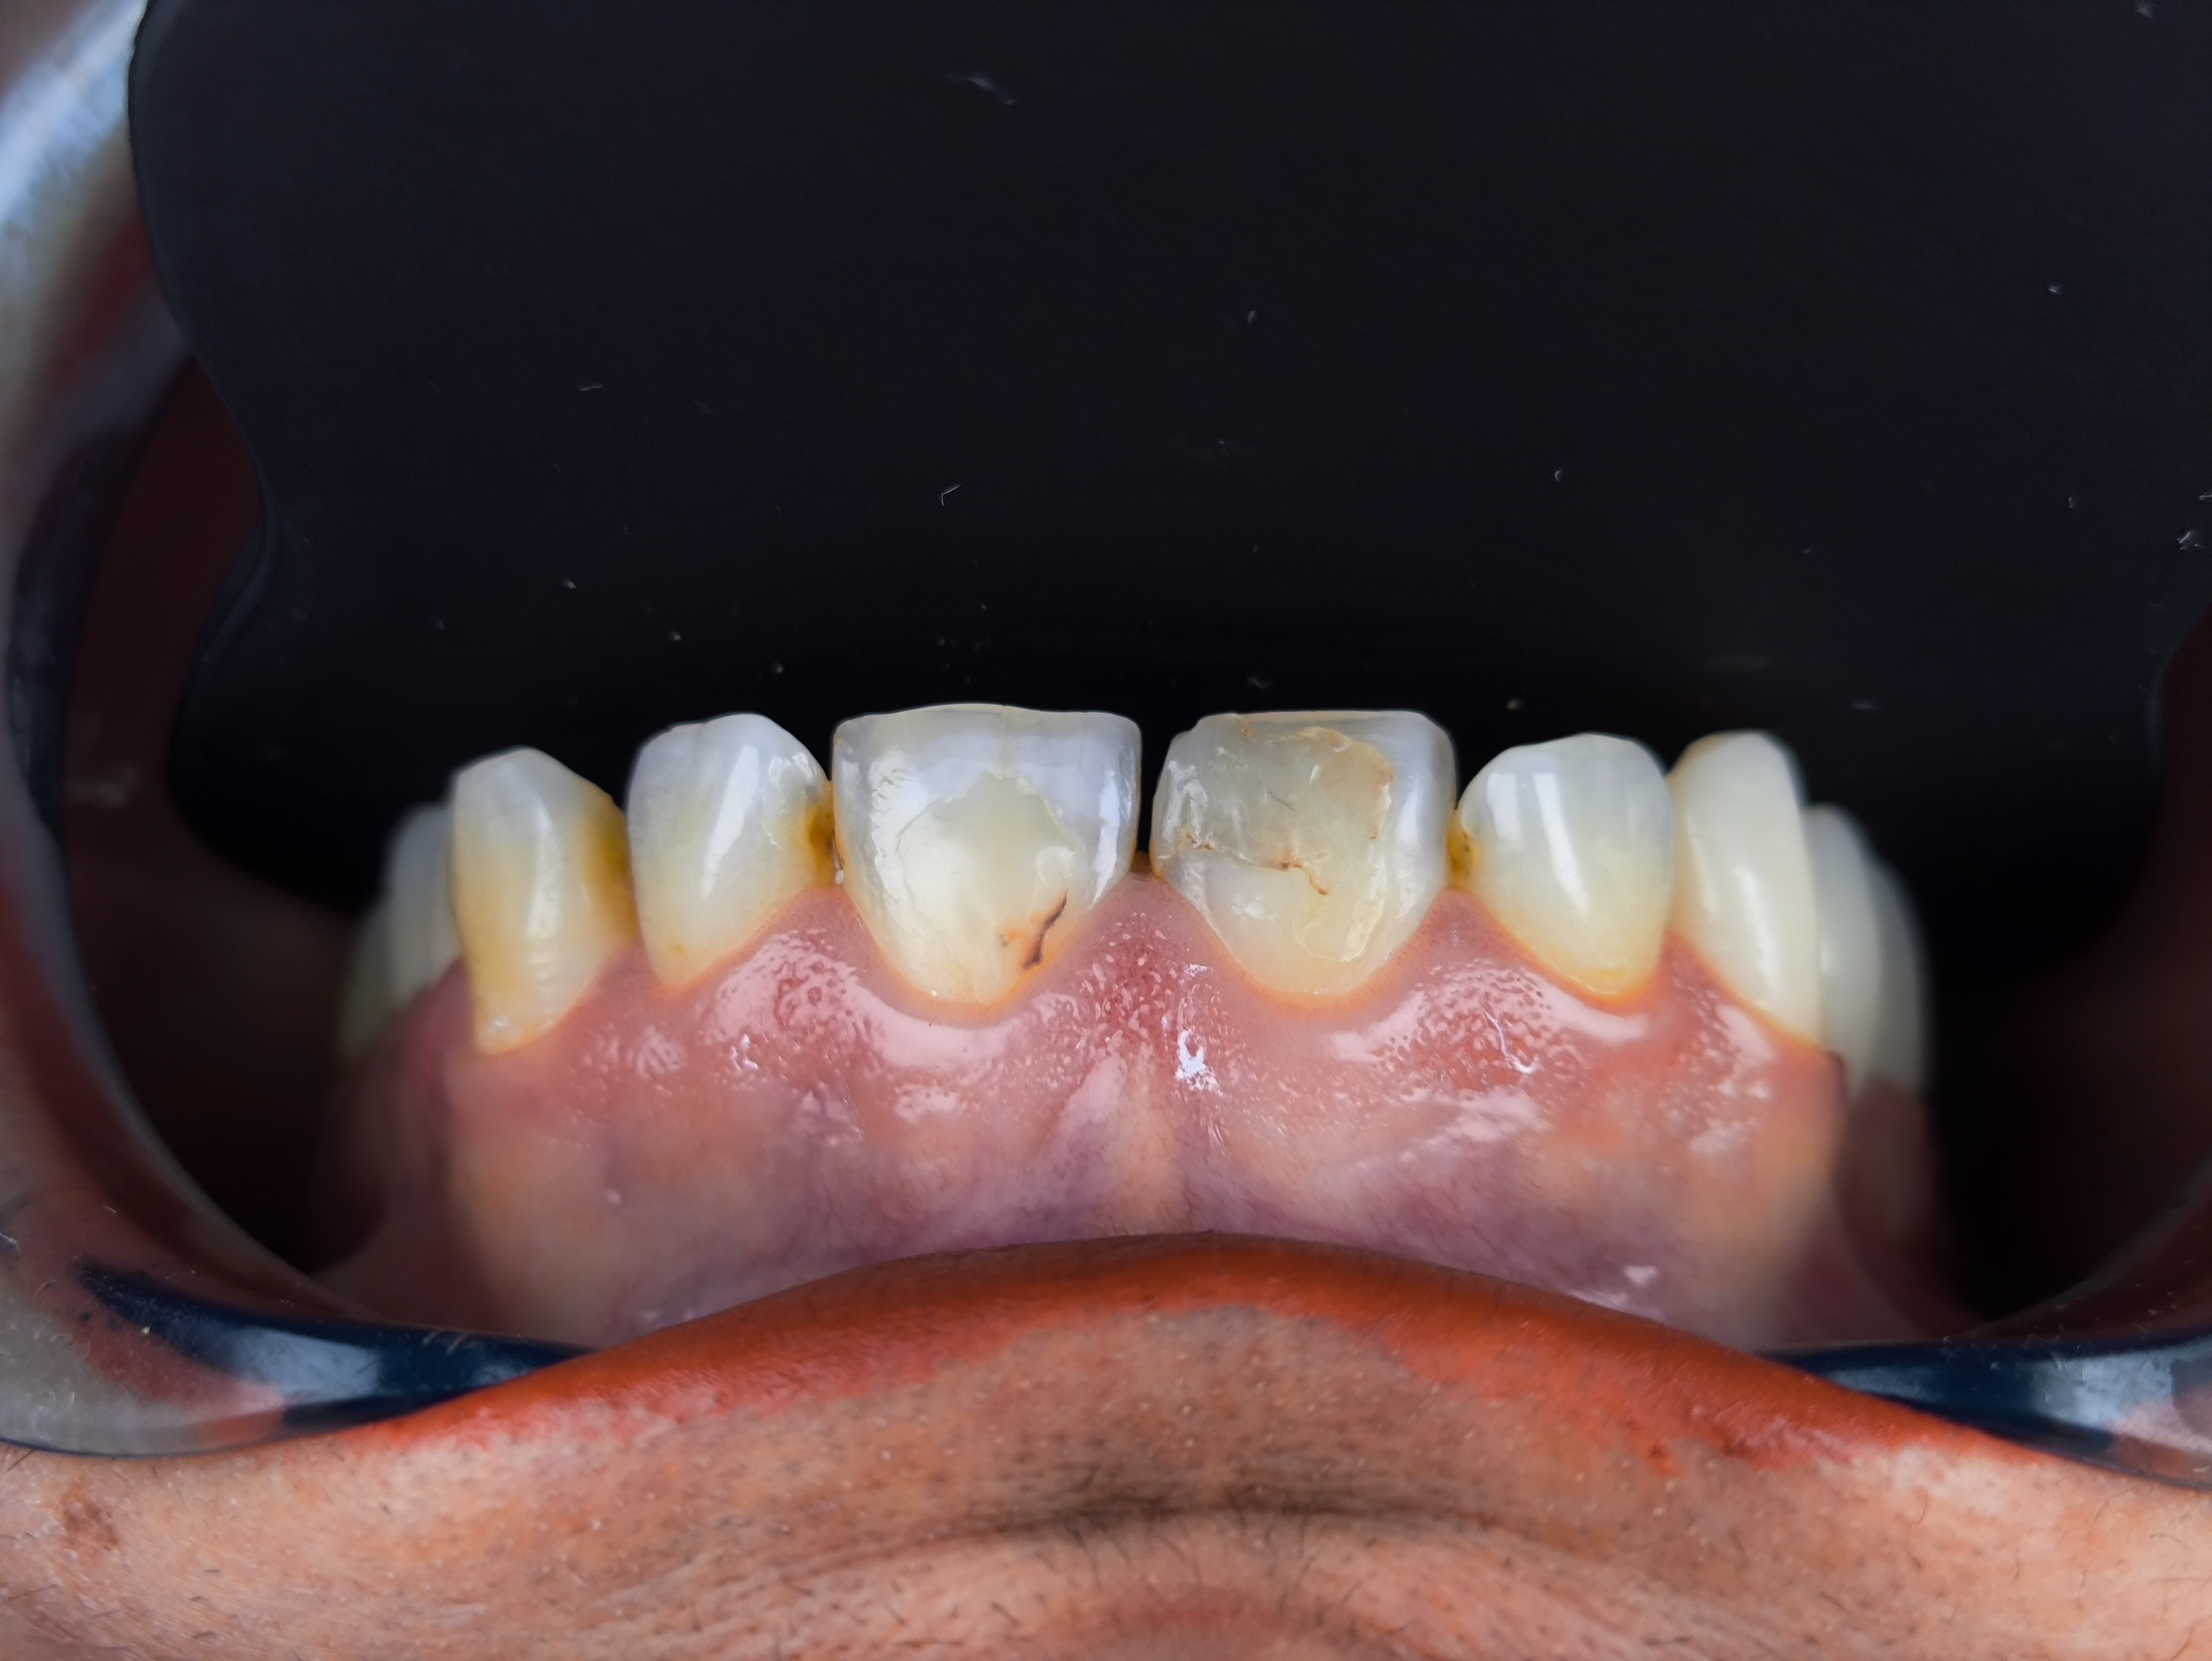

Smile Design Case 2